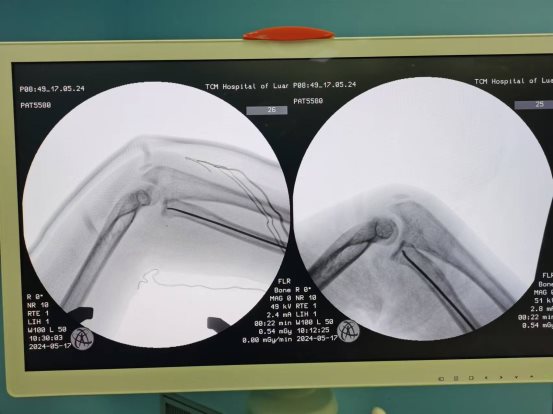

患儿,女,11岁,5月14日因“外伤后右肘肿痛1小时余”入院,术前X线提示右侧桡骨颈骨折,O’Brien分型Ⅱ型,入院后我科陈义权主任立即和张浩医生采用中医特色骨折夹板固定骨折处,于5月17日予右桡骨颈骨折闭合复位弹性髓内钉内固定术,术中我科陈义权主任采用Metaizeau技术,在腕部做一长约1cm切口,利用弹性髓内钉闭合复位骨折端。术后3月复查,骨折端基本愈合。我科成功将中医特色治疗与小儿骨折微创治疗技术完美结合。

图3、4:术中透视下X线